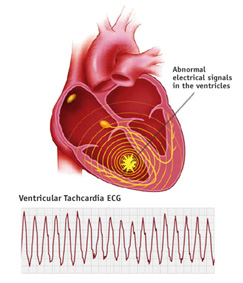

Electromagnetic fields of all kinds (radiofrequency/microwave, dirty electricity) knock calcium ions off the cell membrane. This accounts for the wide variety of effects seen with exposure to smart meters because calcium acts like a neurotransmitter. Thus, your heart, your gut, your brain, your muscles, and your hormones can be affected. In general, the first place that is harmed is the place where you have the least resistance. Over time, various other organ systems will be harmed. We go into this in great detail on our Health: The Science page.

Caroline says: “Life can change in a heartbeatâliterally. That’s what happened for me. We didn’t know a smart meter had been installed on our home until we got our electric bill about a month after the meter was installed. Was I worried? Just the oppositeâ I was excited, having heard only great things about them.”

Caroline had been waking up with a racing heart for a few weeks before she got her electric bill. “I couldn’t figure it out. Was I having bad dreams? Soon, I began noticing irregular heart palpitations during the day. I was also experiencing insomnia, headaches, ear pain, difficulty hearing, flu-like symptoms, numbness, excessive flatulence and abdominal pains, and rashes, to name a few.” Her children began to get many of the problems. She thought maybe they all had the flu. Her husband seemed to be fine. Then, he had two weeks off work and began to develop rashes.

Why do smart meters cause such a vast array of health effects? The effect of EMFs on calcium can explain the vast majority of health effects, first because calcium plays a critical role in the transmission of nerve signals and secondly because calcium is the glue that holds the cell walls together. EMFs can easily knock the calcium ions off the cell membrane.

An excess calcium causes the transmission of unnecessary nerve signals. This accounts for things like heart palpitations, insomnia, and anxiety, and ADD. You can read about this in greater detail on our Health: The Science page, where we have numerous links to research on this phenomenon.